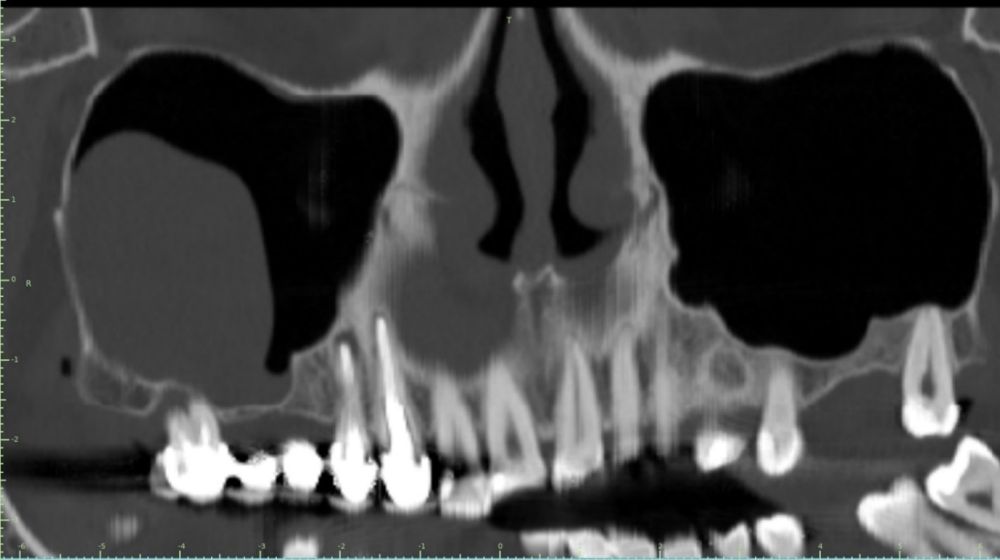

En la exploración radiográfica mediante escáner se apreció una lesión apical de pequeño tamaño en el 1.4 y una escasa disponibilidad ósea. Además, se observó imagen radioopaca cupuliforme de 3 x 2,8 cm en el seno maxilar derecho, compatible con un pseudoquiste sinusal (Figura 2). La extensión craneal alcanzaba la mitad superior del seno maxilar y el volumen de la lesión (5 cm³) era aproximadamente ⅓ del volumen sinusal (Figuras 3 y 4).